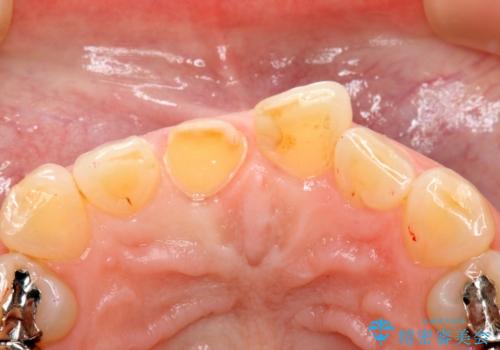

- 上顎前歯の歯冠部が破折した患者様です。神経にまでは到達していなかったので精密根管治療は行わず、審美性を考慮し、オールセラミッククラウンでの治療を選択しました。

歯ぎしりのある患者様なので、就寝時にマウスピースを着用するようにお伝えしています。